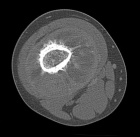

M.D. - 5 year old female with right thigh pain for one month, her parents have noticed swelling in her thigh over the past week, she began limping a few days ago and now is reluctant to bear weight on her right leg